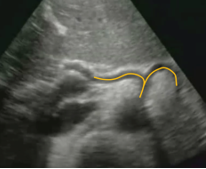

Aorta Seagull Sign Still image